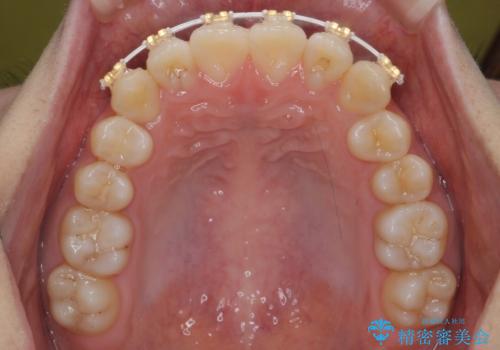

先にワイヤーで部分矯正を行ってから、インビザラインの部分矯正を行いました。

先に難しい部分をワイヤー矯正することで、インビザラインの部分矯正コースで短期間で予算も抑えて確実に治すことができます。

専門的な話になりますが、下顎の小臼歯は円柱状の形をしており、インビザライン単独では捻転はほぼ治りません。

今回は左下の小臼歯が捻転が強く、そこが反対咬合になっていたため事前に部分矯正を行いました。